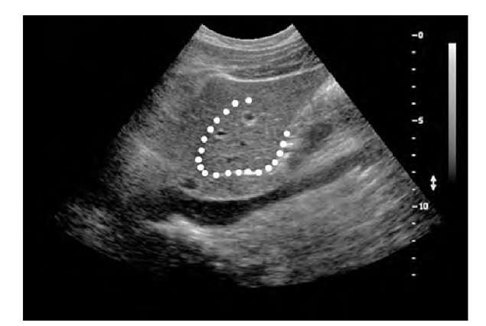

纹理分析的应用范围包括纹理分类,如遥感(图5),纹理分割,如生物医学成像(图6)。它还被用于图像合成和模式识别任务,如从照片中识别绘画。

下图(图6)显示了二流腔静脉的超声图像(图的下三分之一处为钝区)。肝脏的分割,被白色斑点包围的区域,显示出与周围组织相比独特的纹理。